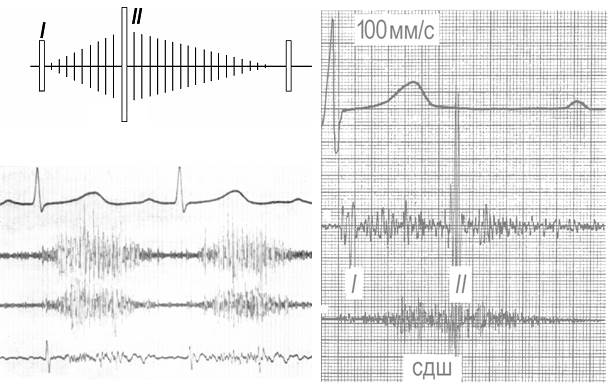

Рис. 4. Шум митральной недостаточности:

Вверху слева – границы относительной тупости сердца по данным перкуссии, точка максимальной громкости шума (кпасный кружок) и зона проведения (густота точек соответствует громкости шума),

Вверху справа – ЭКГ II, ФКГ (высокая 1, средняя 2 и низкая частоты) - пансистолический шум. На средней и низкой частотах – картина суммационного ритма галопа: I, II, III+IV тоны.

Внизу справа – два варианта шума (схема). I,II – тоны сердца, СШ – систолический шум.